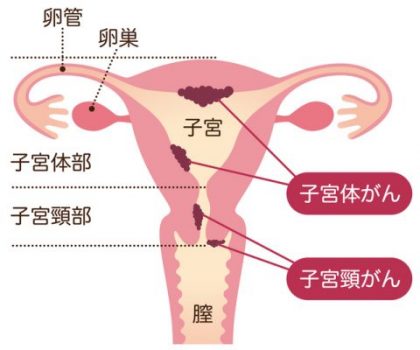

(図 gan-mag.comより)

4月9日は”し きゅう=子宮”の日。子宮頚がんワクチン・子宮頚がん検診の陰に隠れ、あまり話題になりませんが、中高年女性の子宮内膜がん(子宮体癌)が増え続けています。子宮内膜がん(子宮体癌)は稀に若い女性にも発生します。

厚生労働省の資料によると、2020年度の子宮頚がん検診(一般的に「子宮がん検診」と呼ばれている)の受診率は15.2%です。しかし、あくまで子宮頚がんだけで子宮内膜がん(子宮体癌)は「子宮がん検診」に含まれていません。(「子宮がん検診」さへ受ければ大丈夫と言うのは、大きな間違いなのです)